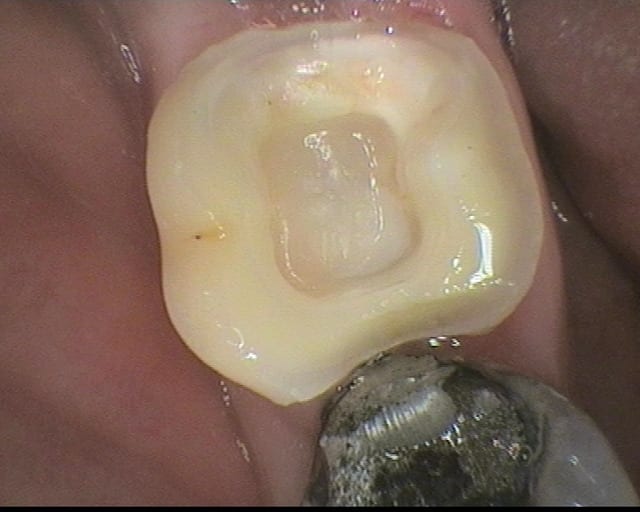

pour répondre à la question initiale du post, un cas de molaire dépulpée non couronnée.

Mise en place d'un cvimar (fuji II lc) en recouvrement de l'entrée canalaire puis onlay Empress collé.

Patiente de 21 ans.